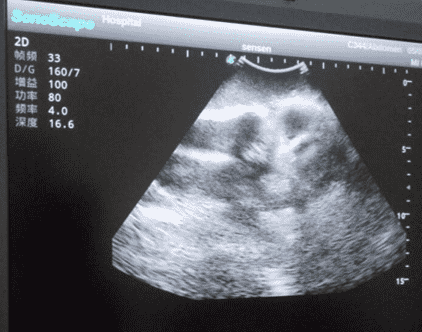

2) Real clinical ultrasound images with clear anatomical structures like femur, joint cavity, etc.